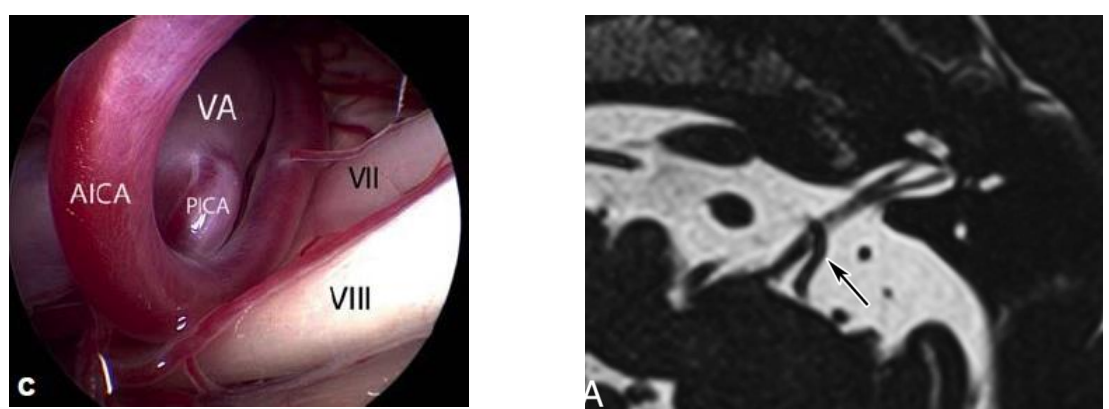

Neurovasculaire compressie van de n. VIII:

AICA → meestal

PICA → 2de meest

Arteria labyrinthis

Veneus bloedvat

Tumor

Cyste

Trauma

MRI waarop neurovasculair conflict vastgesteld wordt

OPGELET: MRI is niet voldoende om de diagnose te kunnen stellen aangezien er frequent (70%) sprake is van aasymptomatische neurovasculaire compressie

➔ Neurovasculaire compressie is niet pathognomonisch!